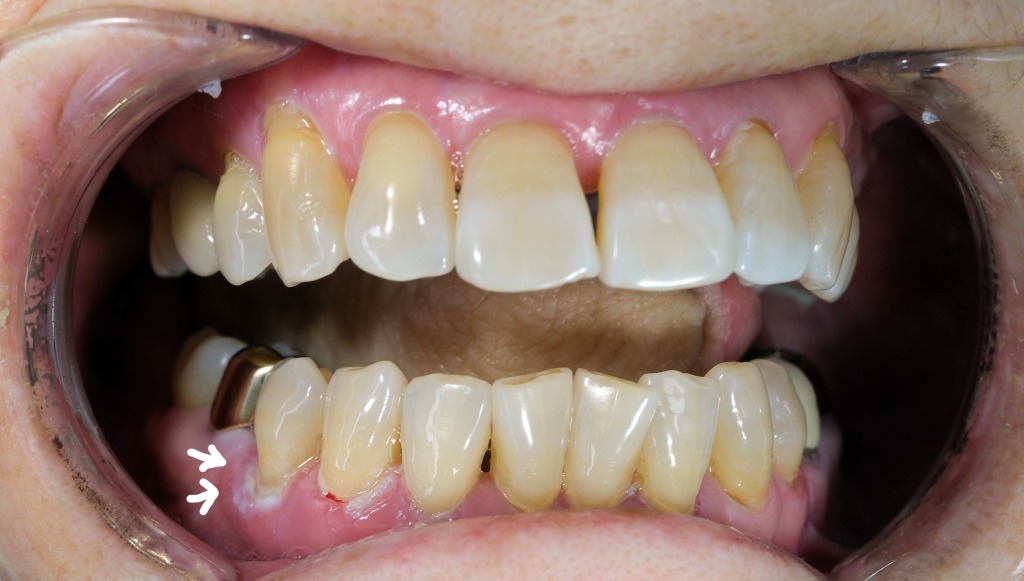

오늘 소개드릴 사례는 기존에 설암으로 외부병원에서 수술을 잘 받으시고 재발없이 경과관찰 하시던 도중, 잇몸에서 새롭게 암이 진단되어 오셨던 여성 환자분입니다.

CT/MRI 등의 검사를 통해, 다행하게도 아직 하악골을 침범하지는 않은 것으로 판단된 조기의 치은암으로 진단하였고, 이 경우 변연절제술(marginal mandibulectomy)가 가능합니다.

변연절제술은 하악골을 침범하지 않았거나, 골막 침범에 국한된 수준의 조기 치은암에 적용가능한 술식입니다. 하악골 변연절제를 넘어 부분절제부터는 고도의 재건수술이 동반되어야 합니다.